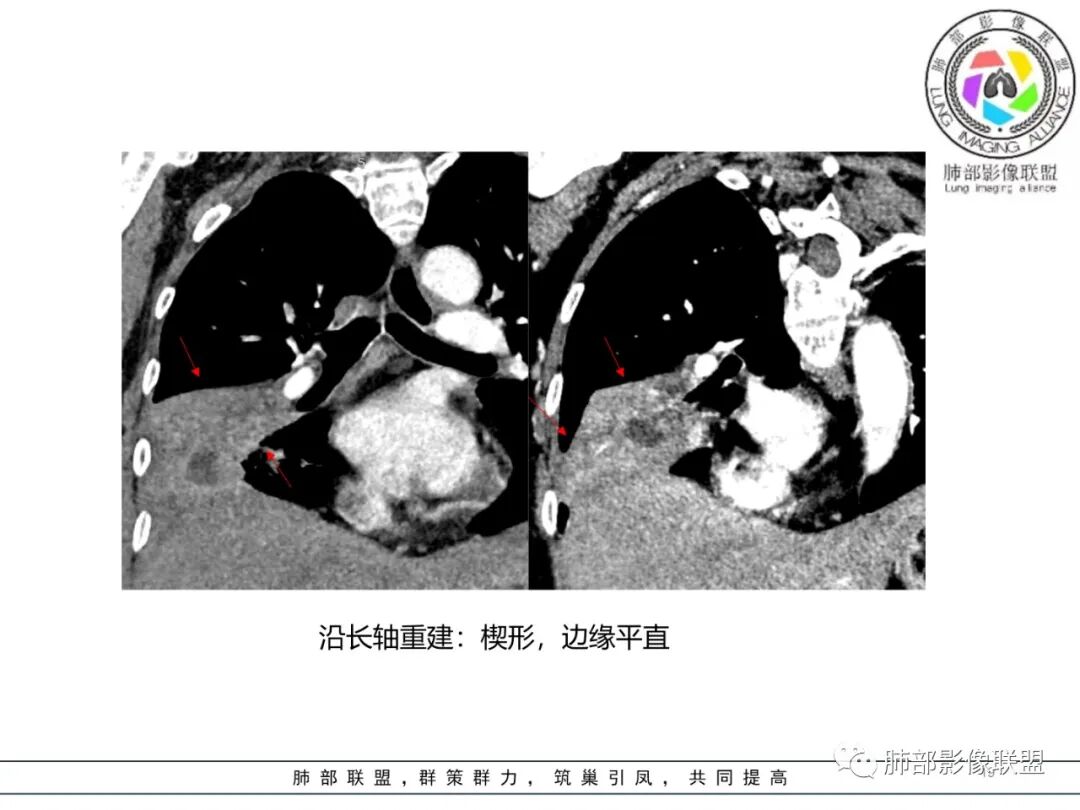

本来还有长轴,边缘

需要重建

三、补充重建图像

南边:跨叶、楔形/边缘平直、支气管壁无破坏/连续/局部无膨大、实变区肺动脉走形自然、实性部分均匀、延迟强化、坏死腔内壁光滑/内壁强化环/近端与支气管相通,这些点均支持炎性。所以综合分析:符合炎性。